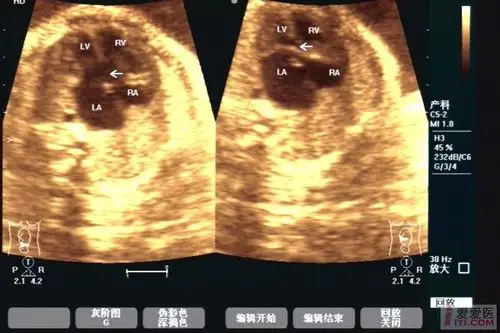

【原创】胎儿发育畸形------ 部分型心内膜垫缺损两例